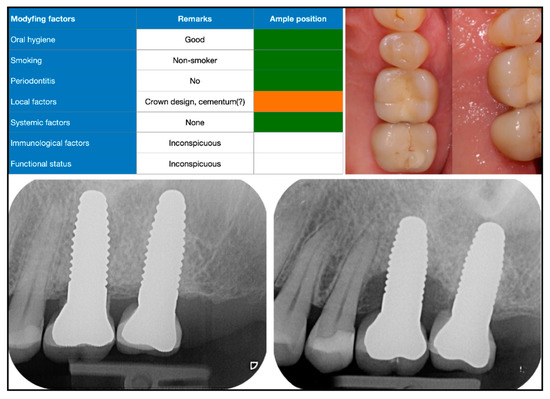

| Interface between crown and implant on radiograph | Number of patients (%) |

| Gap-free | 86 (45) |

| Insufficient | 100 (53) |

| NA | 4 (2) |

| Radiographic form of defect | Number of patients (%) |

| Horizontal bone loss | 84 (44) |

| Vertical bone loss | 59 (31) |

| Marginal radiolucency | 4 (2) |

| No bone loss visible | 38 (20) |

| NA | 5 (3) |